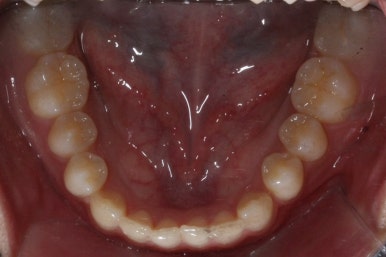

이번 환자분의 경우는 아랫니는 약간 삐뚤함이 있지만 굳이 교정치료를 원하지 않으셨기 때문에 윗니들만 부분교정으로 해결하기로 했습니다.

이상적으로라면 위-아래를 한 쌍으로 해야 교합을 맞추기에 유리하지만 이번의 경우는 윗니만 해도 충분히 교합을 맞출 수 있겠다고 판단하여 부분교정을 하였습니다.

윗니만 하고 싶다고 무조건 윗니 부분교정이 가능한 것이 아니기 때문에 반드시 교정전문의와의 상의를 추천드립니다.

아래치아는 여전히, 당연히 장치가 붙지 않은 채로 그대로 둡니다.

썩은 유치 대신 영구치 송곳니는 매우 자연스럽게 위치되었습니다. 아랫니는 교정하지 않았기 때문에 약간 삐뚠 느낌은 남아있지만 맞물림은 크게 문제가 없게 마무리 되었습니다.